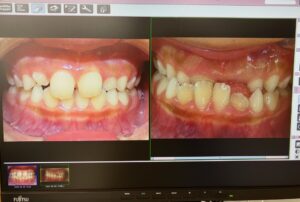

1年弱でうけ口もあちこち向いていた歯も整ってきました。まだまだ生え変わります。ちゃんと綺麗に並んでくると思います。